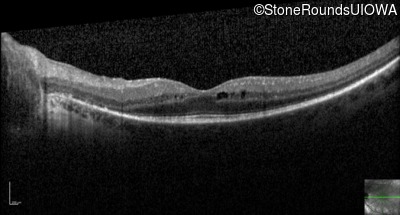

Optical Coherence Tomography - Left - 20/32

Exemplar / OCT Stack